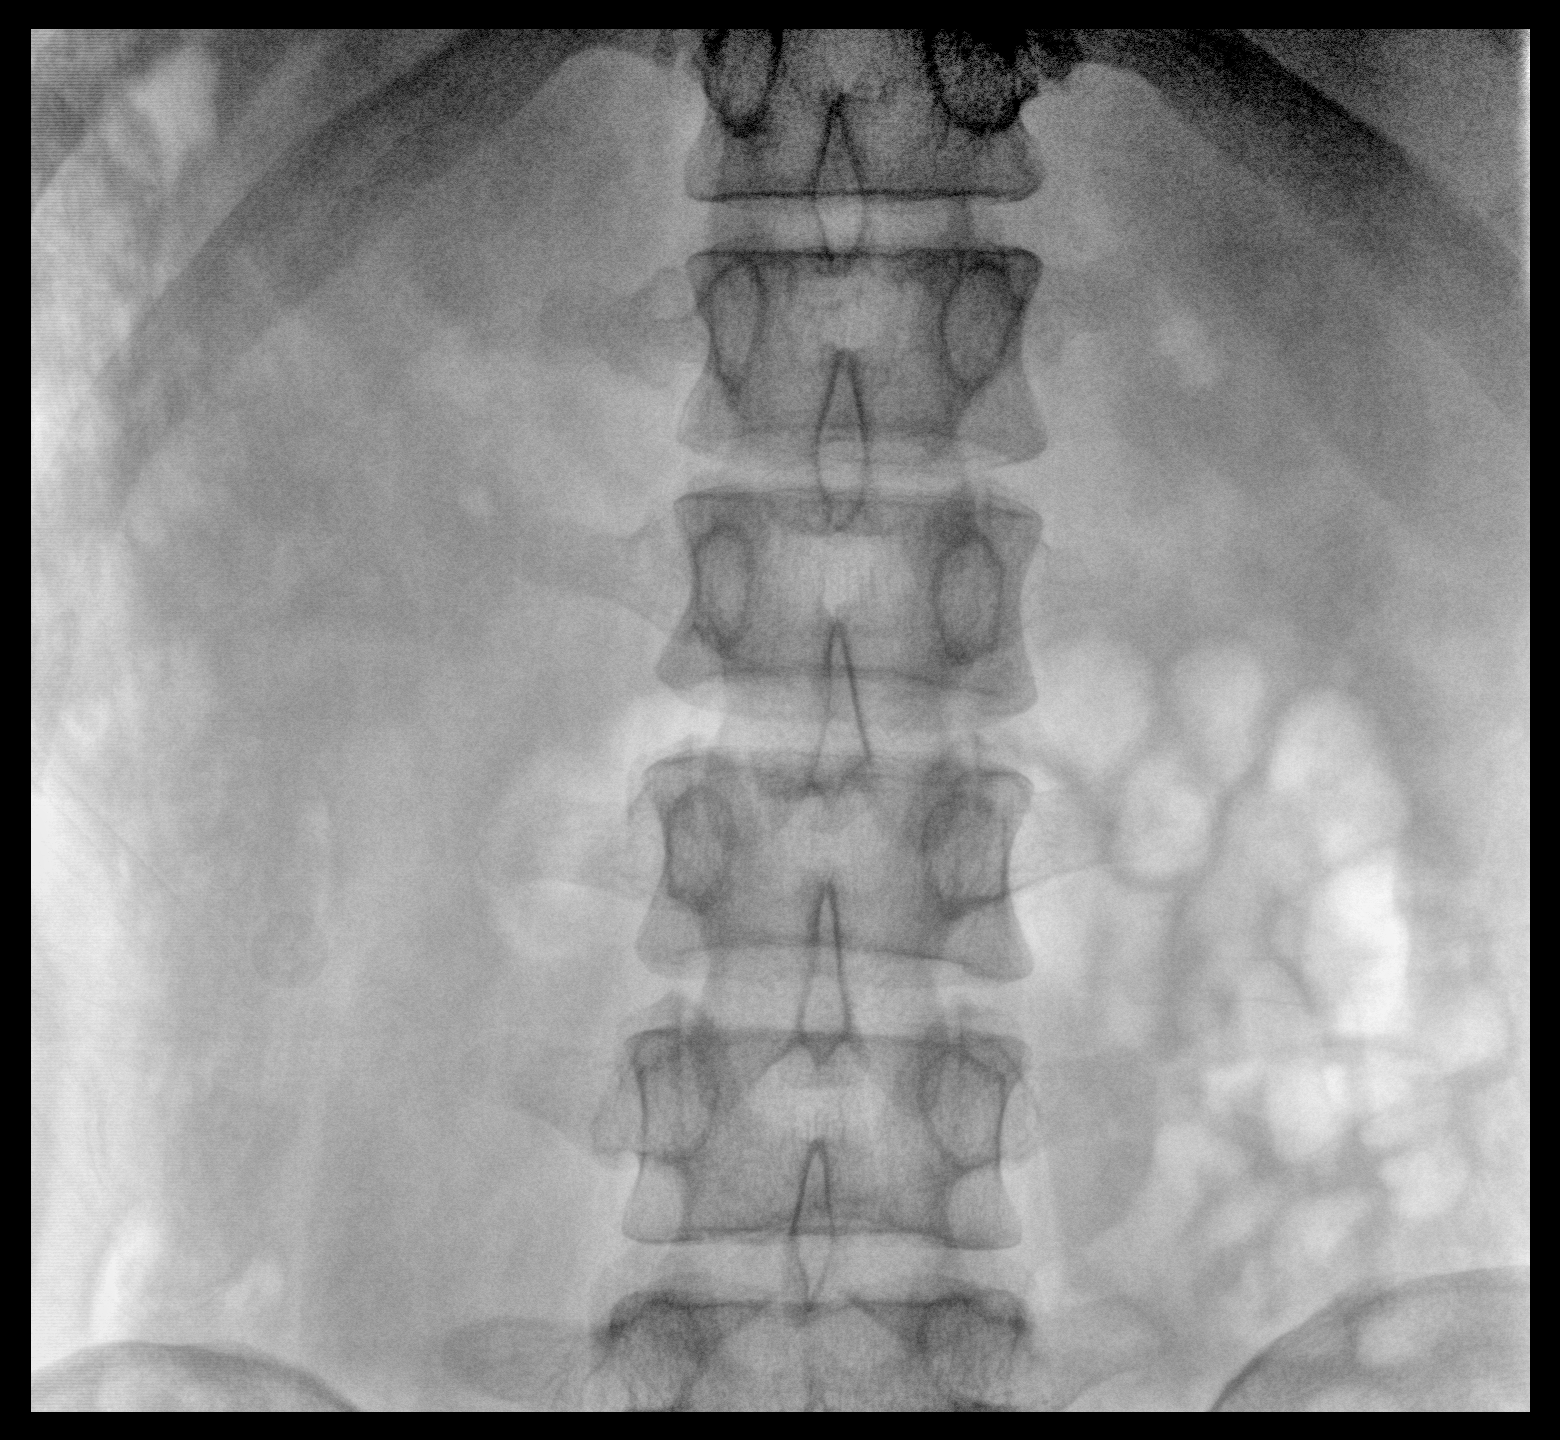

大尺寸動態(tài)平板探測器,高DQE、低噪聲、圖像清晰。采用多分辨率圖像增強處理技術(shù),不同部位不同圖像處理算法,滿足客戶多樣化的需求。

圖形化操控界面設(shè)計:設(shè)有多種人體特征攝影參數(shù),操作簡便。雙向紅光十字定位系統(tǒng):實現(xiàn)無射線下的高效定位。信息共享:遵循DICOM3.0格式接口,可無縫對接云PACS系統(tǒng)。